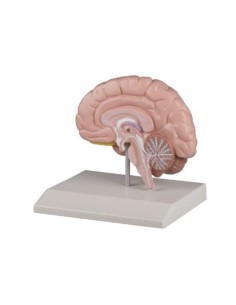

Dal cranio in 22 parti con incastri magnetici ai modelli di colonna vertebrale, da quelli di articolazioni a quelli di cuore, ogni pezzo della nostra collezione è progettato per un’immersione totale nello studio dell’anatomia umana. I nostri modelli, realizzati tramite scansioni di ossa vere, garantiscono un’esperienza tattile autentica e una fedeltà di peso quasi identica agli originali.

Essenziali per studenti e professionisti, i nostri modelli anatomici sono strumenti didattici che permettono di osservare le strutture anatomiche con precisione, eliminando la necessità di dissezioni o studi invasivi. Sono inoltre utili per spiegare ai pazienti le patologie, rendendo la comunicazione più efficace e risparmiando tempo prezioso.